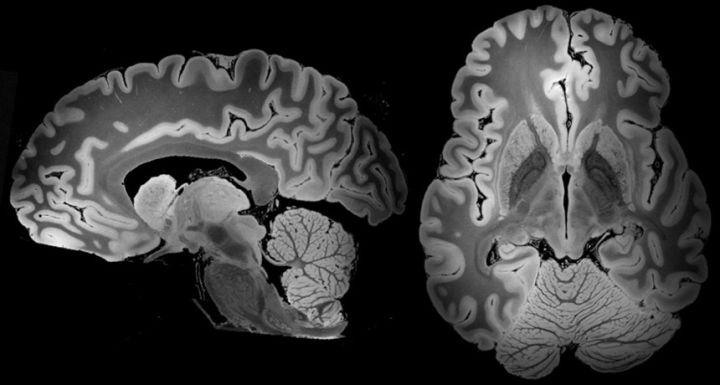

磁共振扫了她5天终于捕捉到人类最详细的大脑图像

大脑的样子

大脑长什么样子

大脑的样子图片

大脑长什么样子图片

大脑的样子真实图片

真正的大脑图片

人类大脑真实图片